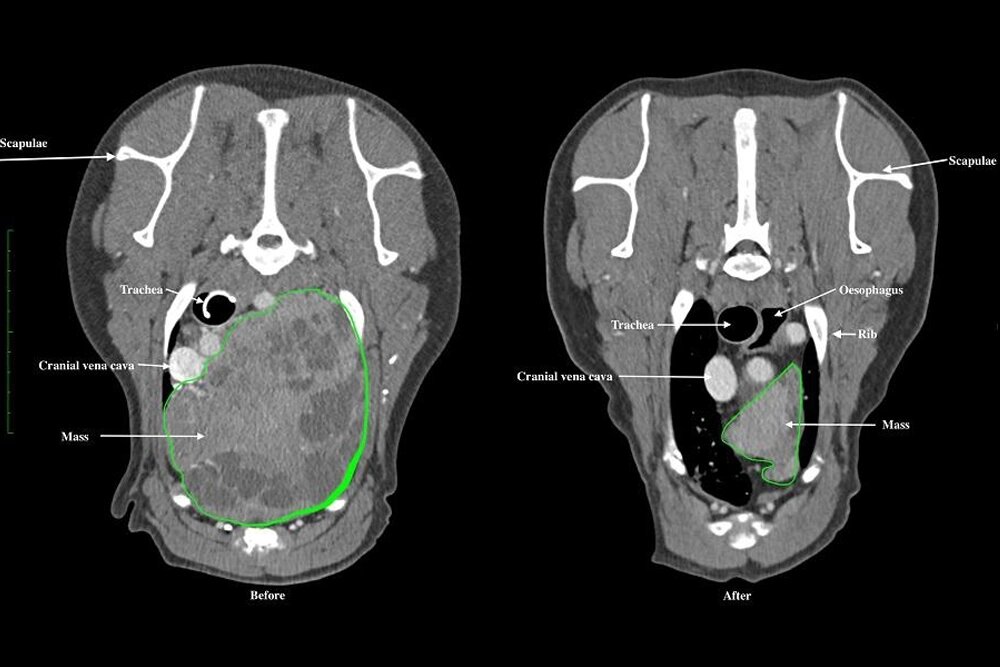

Проведено 20 сеансов лучевой терапии. Контроль по КТ проводился каждые три месяца. Лучевая терапия позволила уменьшить опухоль более чем на 50%.

На фото 1 приведены размеры  опухоли до и после лучевой терапии.

Давление на внутренние органы уменьшилось. Показатель кальция крови пришел в норму.